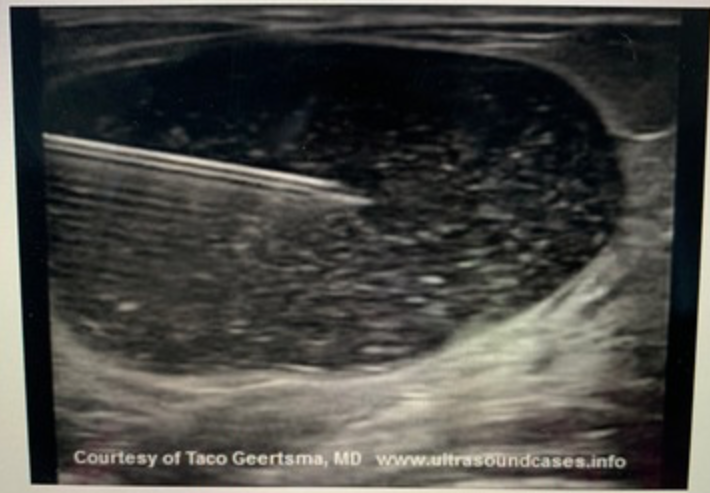

What acoustic artifact is demonstrated on the image?

a. mirror image

b. reverberation

c. propagation speed error

d. posterior shadowing

reverberation